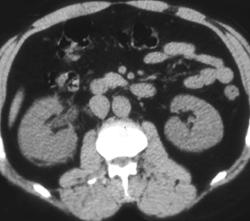

Recurrent Nodes Following Left Renal Nephrectomy for Cancer